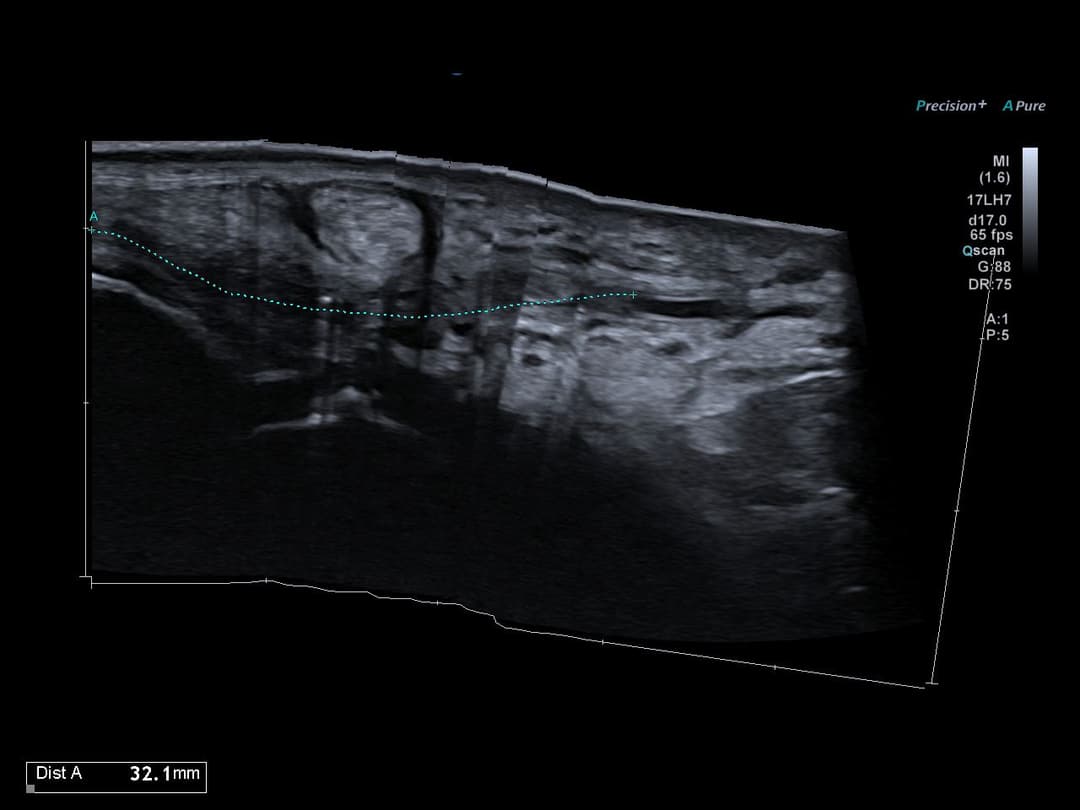

Vue panoramique de la thrombose s'étendant sur 3 cm